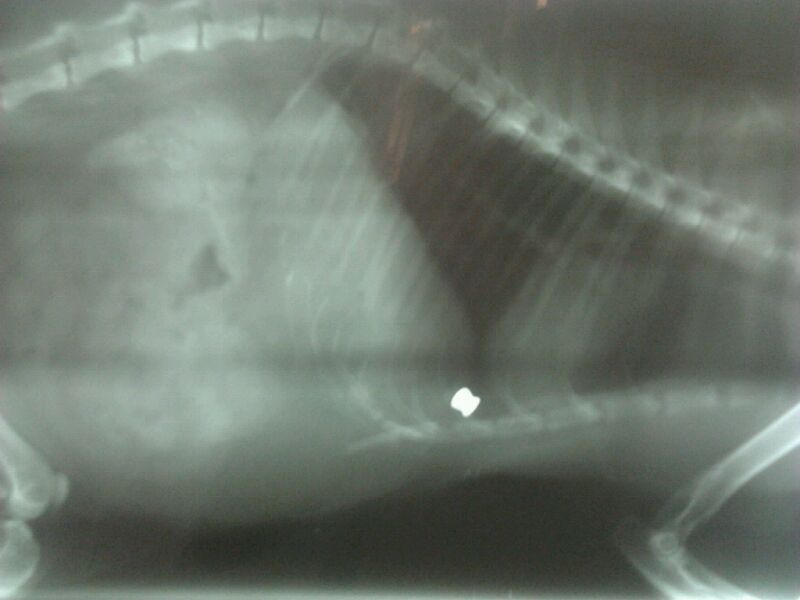

Ahora os adjuntaré las radiografías, para que veáis el balín.

Incluso ha puesto radiografías del balin. Por la penetración en el gato parece una arma potente, además no hay deformación ¿ no ?

Yo no soy nada del tipo forense o veterinario pero me atrevo a compartir con vosotros lo que me parece al ver las fotos, que nadie las tome por una opinión ni acertada ni profesional pues es solo eso, una opinión personal.

Por lo que veo en la foto, su penetración oblicua, el angulo, la deformación o ensanchamiento que se ve en la segunda y sobre todo por el resultado de muerte en el pobre gato me atrevería a asegurar que ha sido producido por una carabina.

Parece entrar en como oblicuo y con angulo descendente, como disparado desde una terraza o ventana colindante, demasiado potente en todo caso para una pistola. Una pistola dudo mucho que pueda hacer eso según sale de fabrica dada su escasa energía, la cabeza plana del perdigón unido al duro pelo del animal mas allá de unos metros solo conseguirían darle un moratón sin penetración, suficiente para producir una lesión, pero no es el caso por lo que a mi me parece.

La deformacion del balin no es mucha.

asi que el arma no tendra mucha potencia. pero si mas que una pistola.

si esta disparando a unos 30 o 40 m con esa penetracion y deformacion del balin , el arma sera un modelo de baja potencia. tipo expo o gamo 400 o 600.

un arma de las llamadas . alta potencia . seguramente hubiera atravesado al gato.